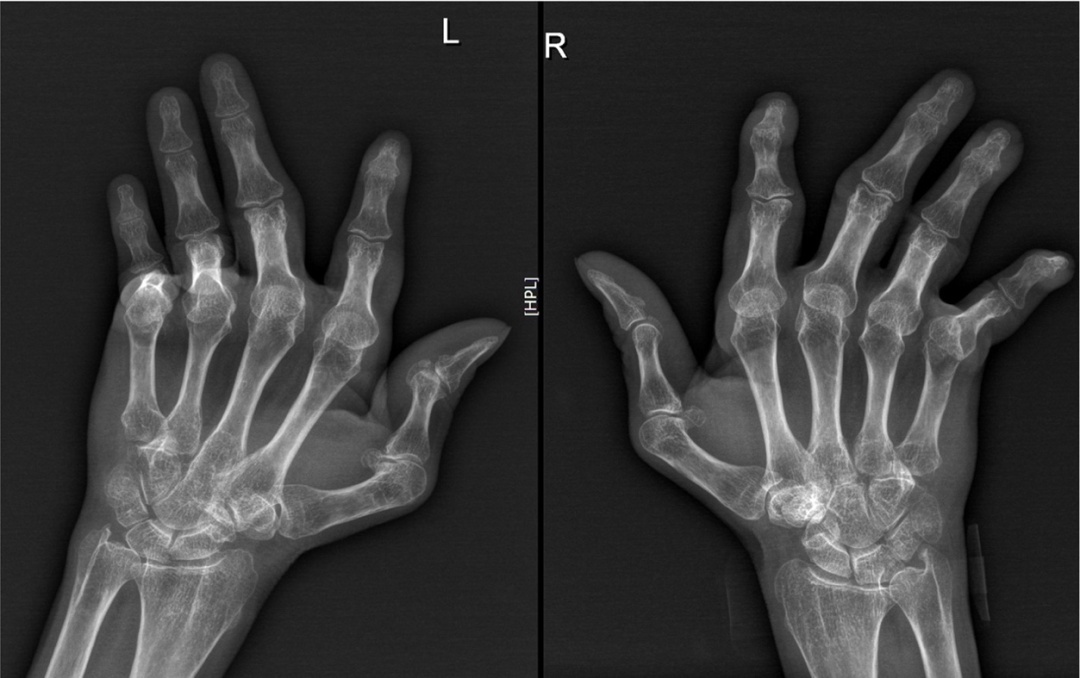

王阿姨双手关节畸形,30年“类风湿关节炎”病史。我数了一下,从掌指关节起双手28个关节肉眼可见24个畸形,“类风关”最多也只有20个!我询问她在30年前有无双手“晨僵”史,她予以否认。我立即拍摄双手X片,无论掌指关节还是远端的指间关节均可见“半脱位”,完全符合“Jaccoud关节病”。Jaccoud关节病常见于系统性红斑狼疮(SLE)、银屑病、皮肌炎等,亦可称为“Jaccoud综合征”。

双手关节畸形:拇指Z字形变,掌指关节尺侧偏曲,指间关节“天鹅颈样”畸形;X片示多发掌指关节、指间关节半脱位,关节面光整无侵蚀,骨密度减低